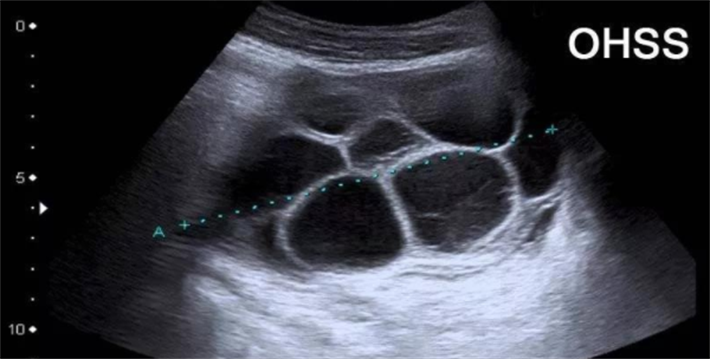

腹水是卵巢过度刺激综合征的典型表现之一。在试管婴儿周期中,部分女性卵巢对促排卵药物产生过度反应,引发一系列以卵巢肿大、毛细血管通透性异常增加为特征的医源性疾病。当毛细血管通透性增加时,血管内的液体和蛋白质会大量外渗,积聚在腹腔中,形成腹水。

从病理生理机制来看,OHSS的核心是血管内皮生长因子的过度产生。促排卵药物刺激卵巢后,黄素化颗粒细胞大量分泌VEGF,导致全身毛细血管尤其是卵巢血管的通透性显著增加。液体从血管内渗出进入第三间隙(主要是腹腔和胸腔),引起腹水、胸水、体重增加、血液浓缩、电解质紊乱等一系列症状。